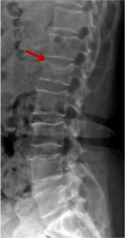

腰椎X線片作為最基礎(chǔ)的影像檢查手段,利于X線穿透人體組織后成像,以其快捷、直觀、價格低廉的特點,X線檢查主要包括腰椎正側(cè)位、雙斜位以及過伸過屈位。主要用于觀察腰椎骨骼的情況,如椎體是否有骨折、骨質(zhì)增生程度、生理曲度的變化、椎體移位的情況等。然而,X線檢查也有它的局限性,無法判斷是骨折的新舊,對于椎體內(nèi)部結(jié)構(gòu)和周圍肌肉韌帶組織(如脊髓神經(jīng)、椎間盤、韌帶等)的顯示不佳,另外X線作為有輻射檢查,孕婦及嬰幼兒謹(jǐn)慎選擇。

箭頭提示腰1椎骨折

箭頭提示腰3椎體滑脫